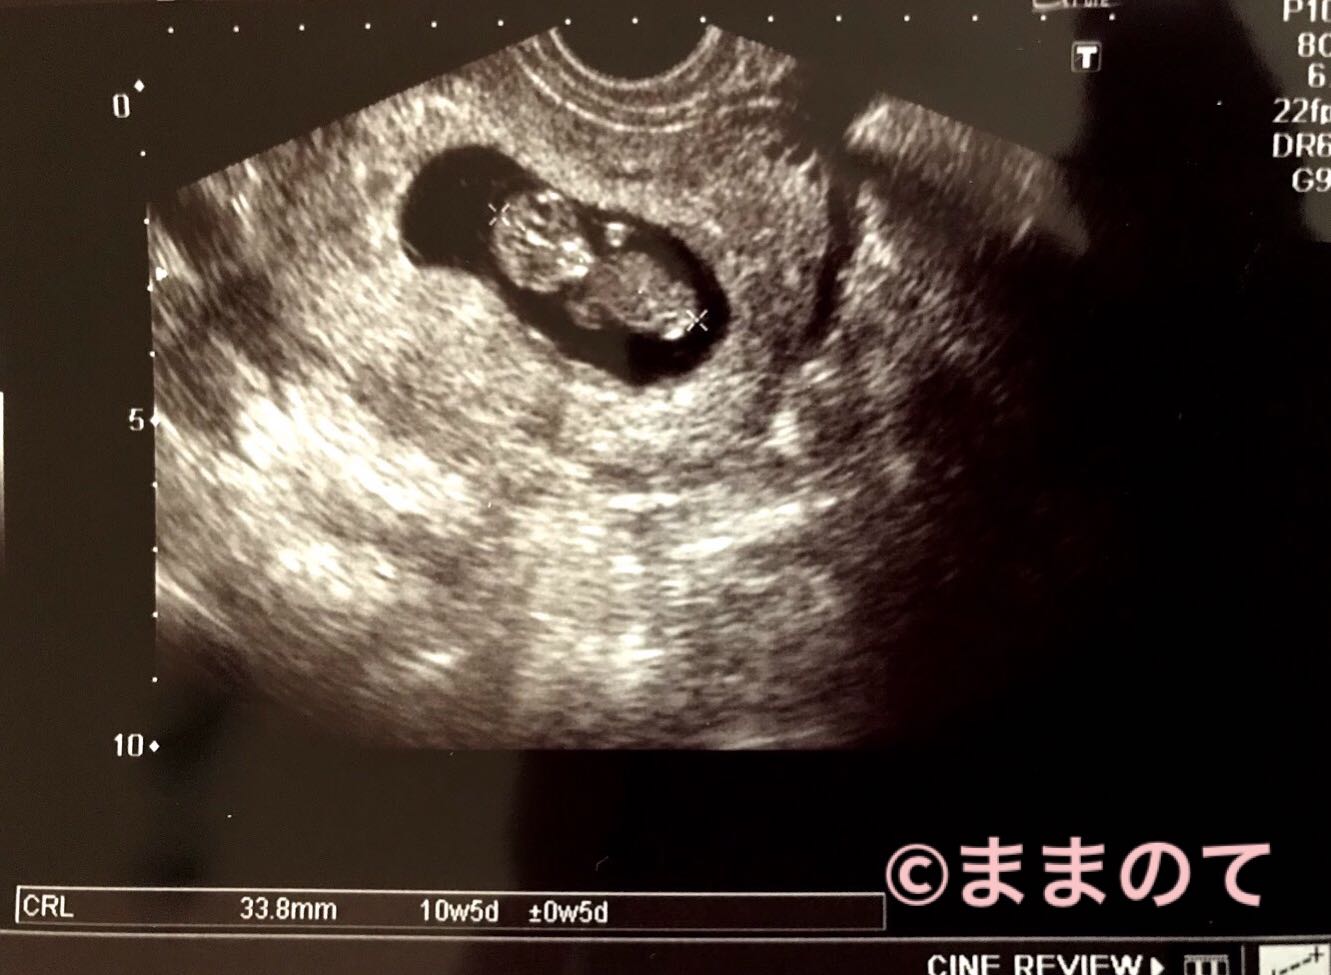

妊娠10週の赤ちゃんのエコー画像

CRL33.8mm、10週5日の胎児のエコー写真です。誤差はプラスマイナス5日。正面をしっかりと見据えているような目の影が印象的です。小さな手足とくびれが確認でき、エコー写真でも人間らしさが伝わってくるので、ママになった実感がわいてきますよ。